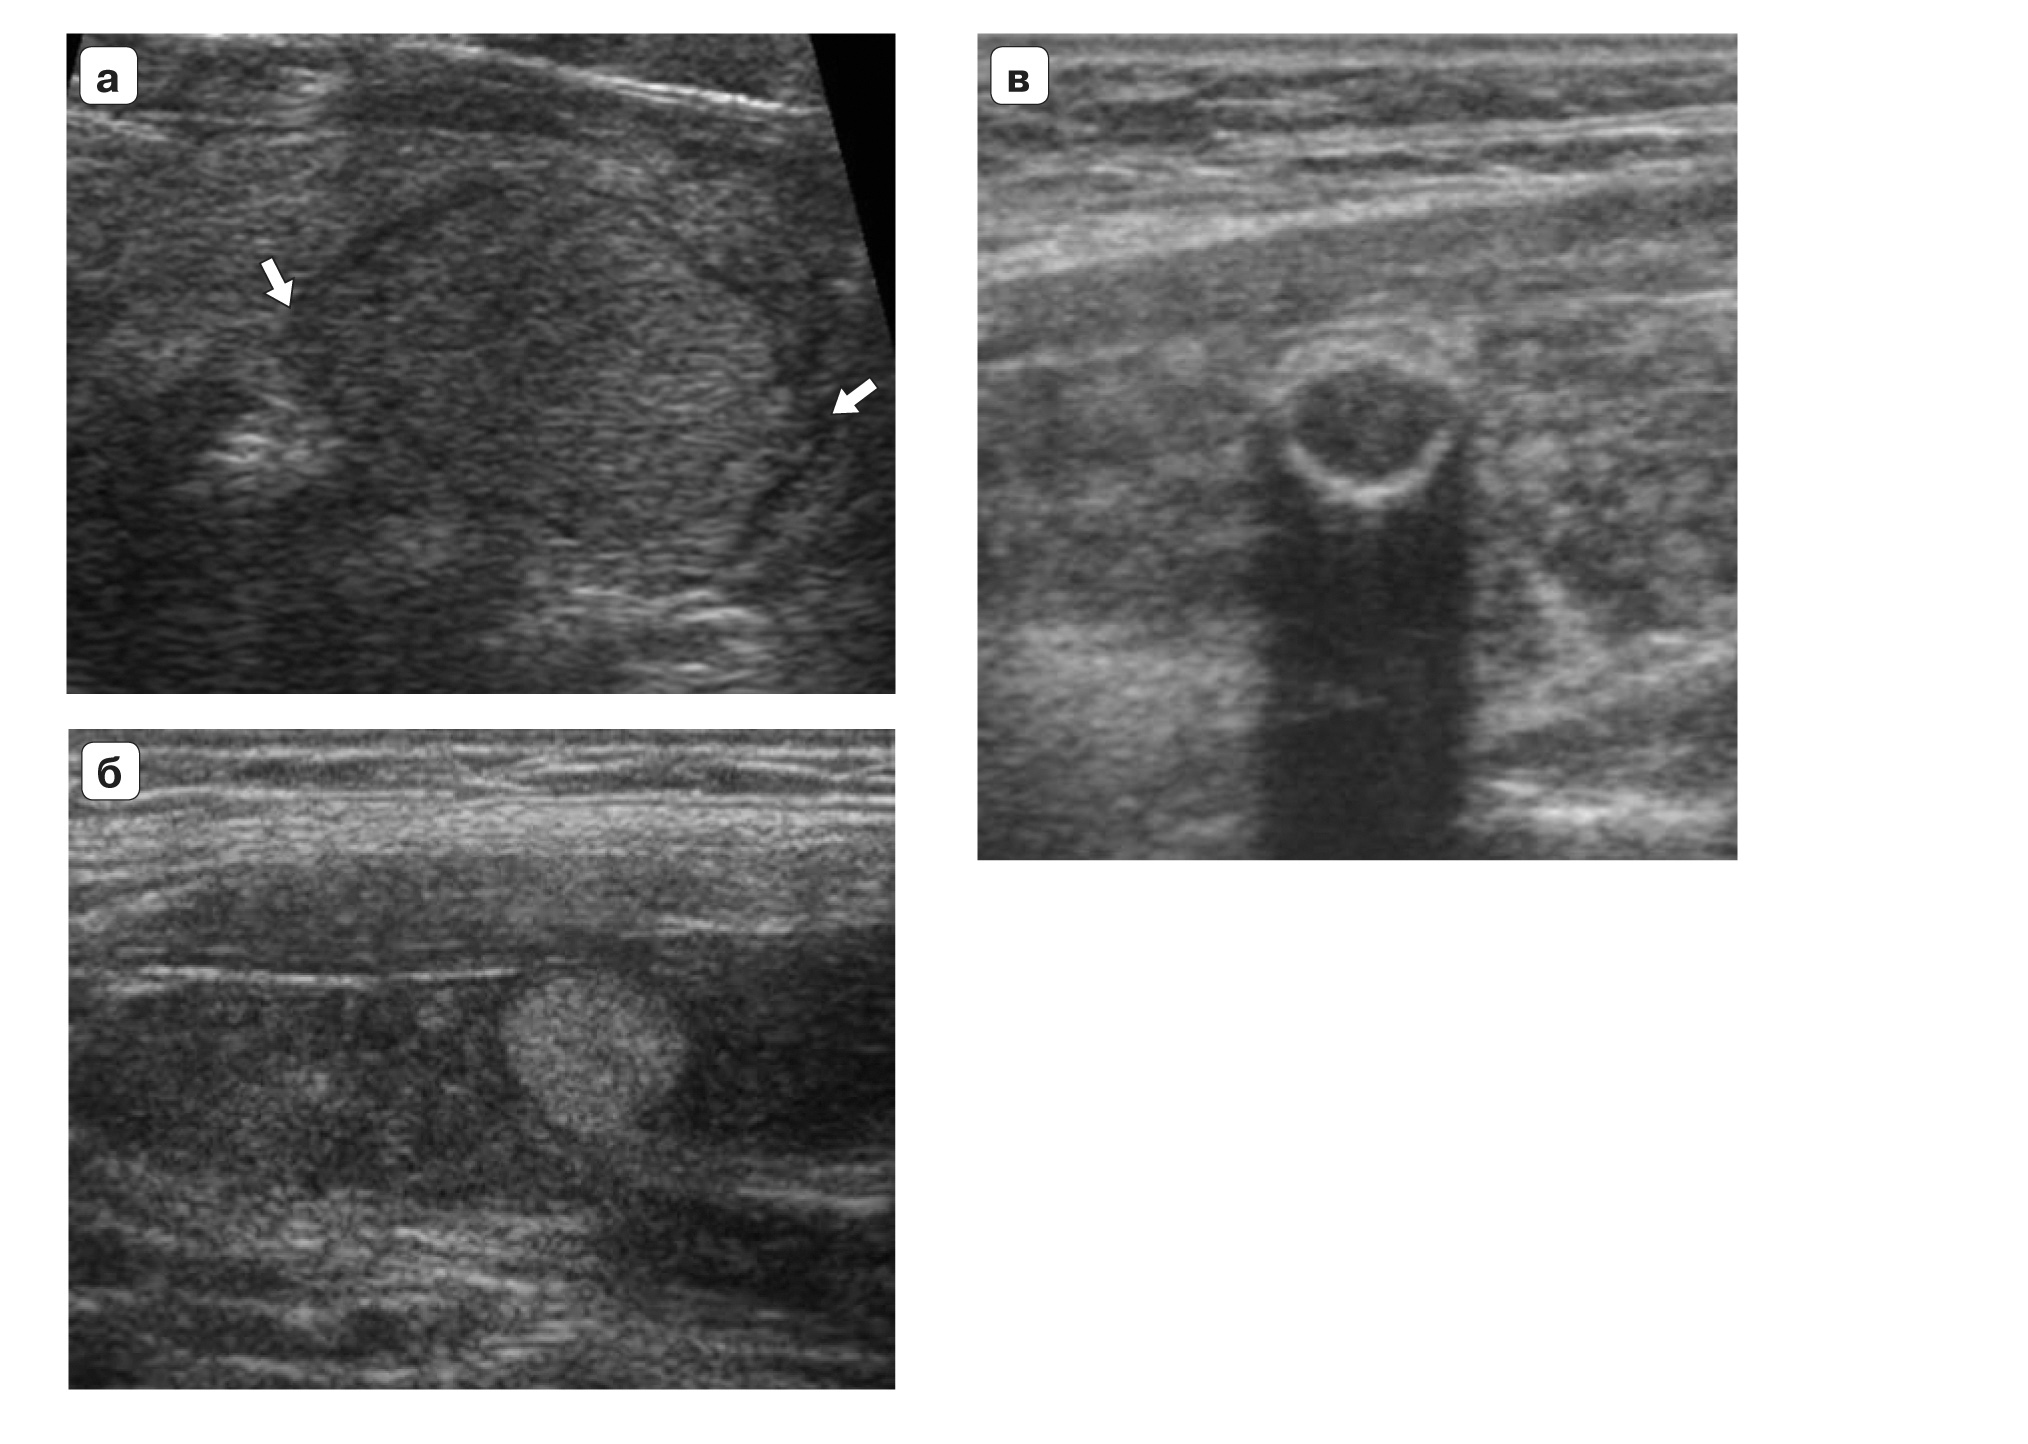

TI-RADS 3. Очаговые структуры, требующие динамического наблюдения без выполнения биопсии (гипер- или изоэхогенные образования с ровными контурами, в том числе на фоне аутоиммунного тиреоидита; кальцинированные узлы по типу “яичной скорлупы”) (рис. 2).

Рис. 2. Категория TI-RADS 3: а – изоэхогенный очаг (стрелки), окруженный тонким хало (узловой зоб); б – гиперэхогенный очаг округлой формы, с четкими контурами, тонким гипоэхогенным ободком на фоне аутоиммунного тиреоидита; в – кальцинированный узел по типу “яичной скорлупы”.